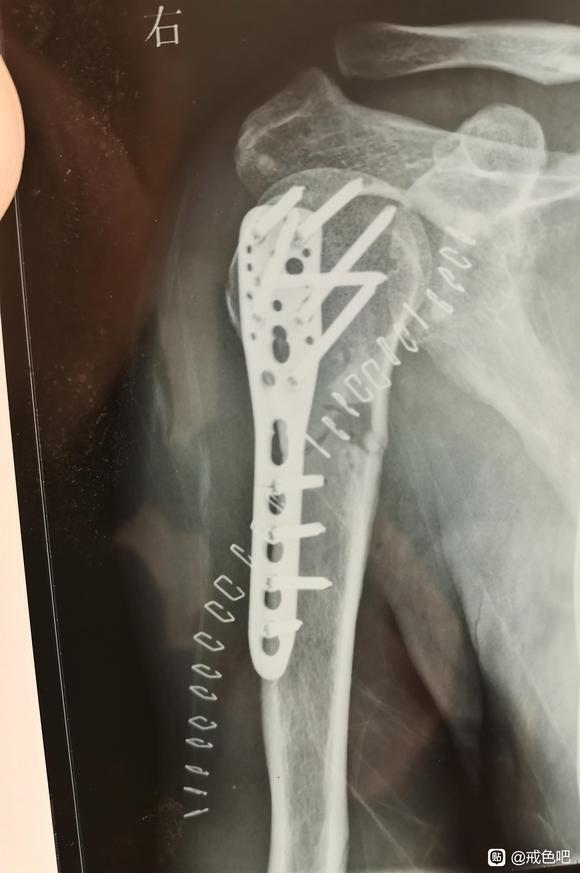

过了一个多月我就得了大恶报,我陪孩子踢球时把胳膊摔断了,当时我以为只是脱臼,而且正有疫情,小区封了出不了门,六点多医院也下班了,不知道是断了以为只是脱臼,就在小区里找了一个写着正骨的地方复位,复位时将胳膊抬起,用力一拖,虽然很疼还可以忍受,脱臼复位后轻松了些,只能动一点,他拿起我的胳膊想捋一下筋,因为不知道断了,一拎起来感觉断的地方痛入骨髓,痛的昏天黑地,见我痛的大叫就放下了,他说是筋伤了需要慢慢恢复,我就回家慢慢养。回家后睡觉只能穿着衣服半躺着,躺累了,稍微翻一点身都疼痛难忍。过了几天,我妈让我去医院拍片看看。在居委会开了看病的出门条,去附近的医院拍了片子,拍之前以为最多只是骨裂,没想到是粉碎性骨折。医生说要做手术打钢板,我问了一位认识的骨科专家说移位不大,恢复好位置后打石膏就可以,因为动手术要做两次,现在做手术打上钢板,一年后在做手术把钢板取出,疫情进不了京,所以就在家等疫情解封后再去治。在家里等的这段时间,食不知味,寝不能安,衣不能解,困极睡会,半夜醒来,如在炼狱,手肿的像馒头,打下喷嚏,震到断骨的地方,能把眼泪疼出来。做的恶事报应没成熟时,感觉生活一片祥和轻松惬意,报应成熟来到时,那真是痛苦难忍,度日如年,需要受的苦头想少一分都难。在家熬了十天左右,丝毫没有解封的意思,就去附近的医院做了手术。打了十根钢钉,缝了几十针,做手术时医生说我这一下摔的够重的。从摔断到治疗一波三折受三次罪,去正骨受一次罪,刚好疫情出不了门在家熬着受一次罪,做手术又受一次罪。做了大恶遭报应惩罚时真是痛不欲生,如在炼狱。